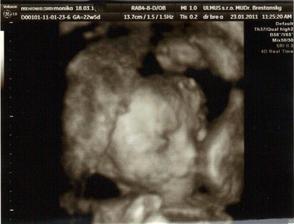

✿♥♥♥♥Bude to dievčatko!!!!! ♥♥♥♥✿

Bude to Stella 🙂

krasne 3D sono 🙂